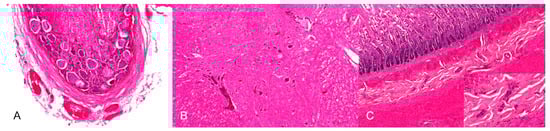

4.4.4. Histopathology

By immunohistochemistry, PRV antigen is mainly present in neurons and glial cells of the brainstem, trigeminal ganglia, spinal cord and abdominal vegetative plexus such as the myenteric plexus [75,76,85,87] (Figure 6). Further, cardiomyocytes as well as fibrocytes and glandular epithelium of the stomach carry PRV antigens [76]. This corresponds to observations in a cat showing antigen positive cells in the intestinal tract and in sympathetic lumbar ganglia [84]. In experimentally inoculated dogs antigen is also present in the pancreas and parotid gland [93], and in the sympathetic stellate, celiac and caudal mesenteric ganglia [78]. Mild to severe nonsuppurative encephalitis mainly affects the brainstem [28,75,76,78,81,84,85,86,87] (Figure 7). Inflammation of the cerebrum [85,88], midbrain and cerebellum [28] may also occur. The inflammatory response is characterized by neuronal necrosis of brain parenchyma and perivascular cuffs consisting of mainly lymphocytes and macrophages. There is glial cell proliferation in the grey and white matter, satellitosis, neuronophagia and more or less intralesional eosinophilic intranuclear inclusion bodies. The adjacent meninges are infiltrated by mononuclear cells, and endothelial cells can be hypertrophic [86]. Inflammatory infiltrates are further detectable in trigeminal ganglia, spinal cord, abdominal ganglia and vegetative plexus as well as in the adrenal gland [75,80,82,84,85] (Figure 8). The heart, lung, kidney, liver, intestinal tract, tonsil are also affected by inflammation, necrosis or hemorrhage [78,81,84,86] (Figure 9). Degeneration and necrosis of cardiomyocytes with mild or no inflammatory reaction can occur in dogs. Focal necrotic areas are evident in the liver, whereas lymphoid depletion as well as hemorrhages are seen in the thymus and lymph nodes (Figure 9). Especially in cats, tonsillary necrosis of the crypt epithelium is reported [84,92]. In scratched skin regions necro-ulcerative dermatitis with subcutaneous edema are present [75,78].

Figure 8.

Inflammation of neural tissues of a PRV-infected dog. (A) Moderate, lymphohistiocytic ganglionitis with neuronal damage, neuronophagia and gliosis. (B) Mild, multifocal lymphohistiocytic myelitis. (C) Inflammation of the myenteric plexus. The ganglia of the myenteric plexus are infiltrated by lymphocytes and histiocytes (inset). (Courtesy: Institute for Veterinary Disease Control, Mödling).

Figure 9.

Inflammation and necrosis in different organs in a PRV-infected dog. (A) Mild lymphocytic bronchiolitis with severe, diffuse alveolar edema. (B) Focal hemorrhagic necrosis in the liver. (C) Multifocal necrosis of lymphocytes in the lymph node resulting in lymphoid depletion, H.E. (Courtesy: Institute for Veterinary Disease Control, Mödling).